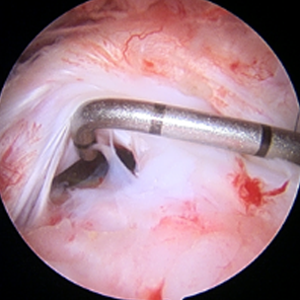

整形外科における手術の役割 肩腱板断裂治療のアルゴリズム 不全断裂 小断裂 中~大断裂 一次修復不能広汎性断裂 保存療法(リハビリ:運動療法/物理療法) 手術療法 関節鏡下腱板修復術 腱移行術、腱移植術、リバース型人工関節 腱板断裂の治療の基本は保存療法ですが、それが反応しない場合には、関節鏡下腱板修復術が適応されます。 修復前 修復後 関節鏡下腱板修復術は「肩に小さな穴を数か所開け、関節鏡で中をのぞきながら縫い合わせる方法」で、私の得意分野です。 不全断裂 小断裂 中~大断裂 一次修復不能広汎性断裂 保存療法(リハビリ:運動療法/物理療法) 手術療法 関節鏡下腱板修復術 腱移行術、腱移植術、リバース型人工関節 縫いきれないほどの大きな断裂には、腱の移植や人工関節が必要になります。 手術を望まない方へは、間葉系幹細胞を用いた再生医療の提供に取り組んでいます。